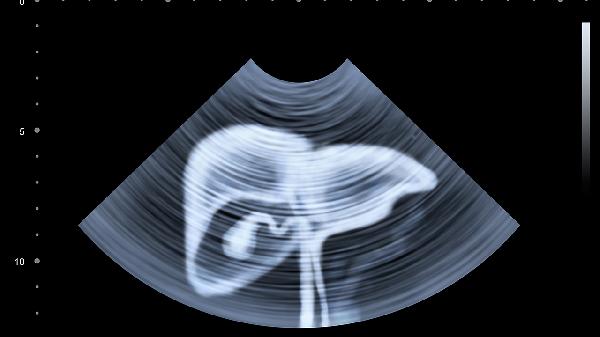

每6个月要做一次腹部B超+甲胎蛋白检测,肝硬化患者需缩短至3个月。建议选择同一家医院检查,便于对比影像变化。